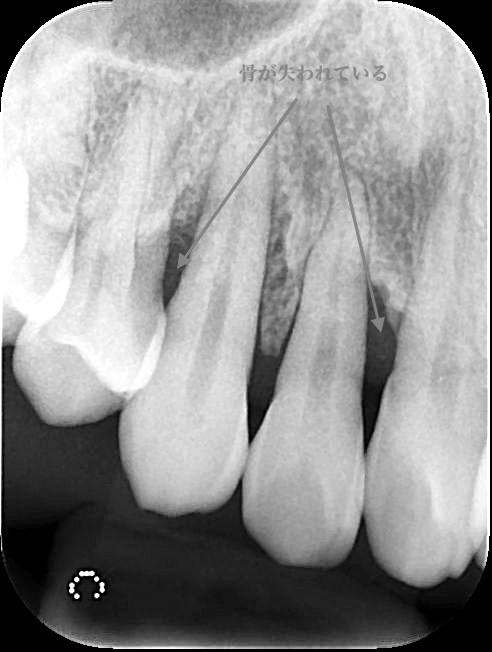

骨の約分が吸収(溶かされている)状態であることから、

重度の歯周病で適切な治療計画を立案するためには、お口の状態を詳細に把握する必要があります。そのために当院では精密な診査診断を行います。歯周病の直接的な原因だけでなく、咬み合わせなどの間接的な原因も把握することによって、治療計画の精度が高まります。

通常抜歯の対象となる歯であっても、歯周組織再生療法を行うことで残せる可能性はあります。もちろん、適応条件はありますが上記の精密な診査診断を行うことで、歯を残せるか否かを判断することが可能です。重度歯周病だから”必ず抜歯”ということはありません。